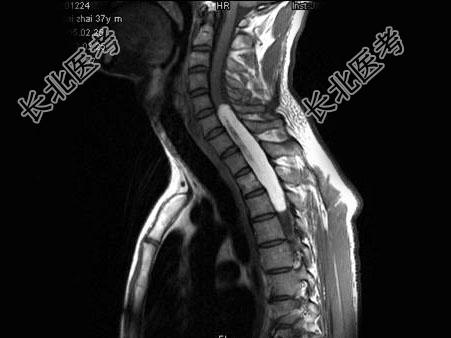

单项选择题男,37岁, 肢体活动不利、酸胀1年余,MRI扫描见椎管内长条形T1和T2高信号, 脂肪抑制序列呈低信号,应考虑为 ( )